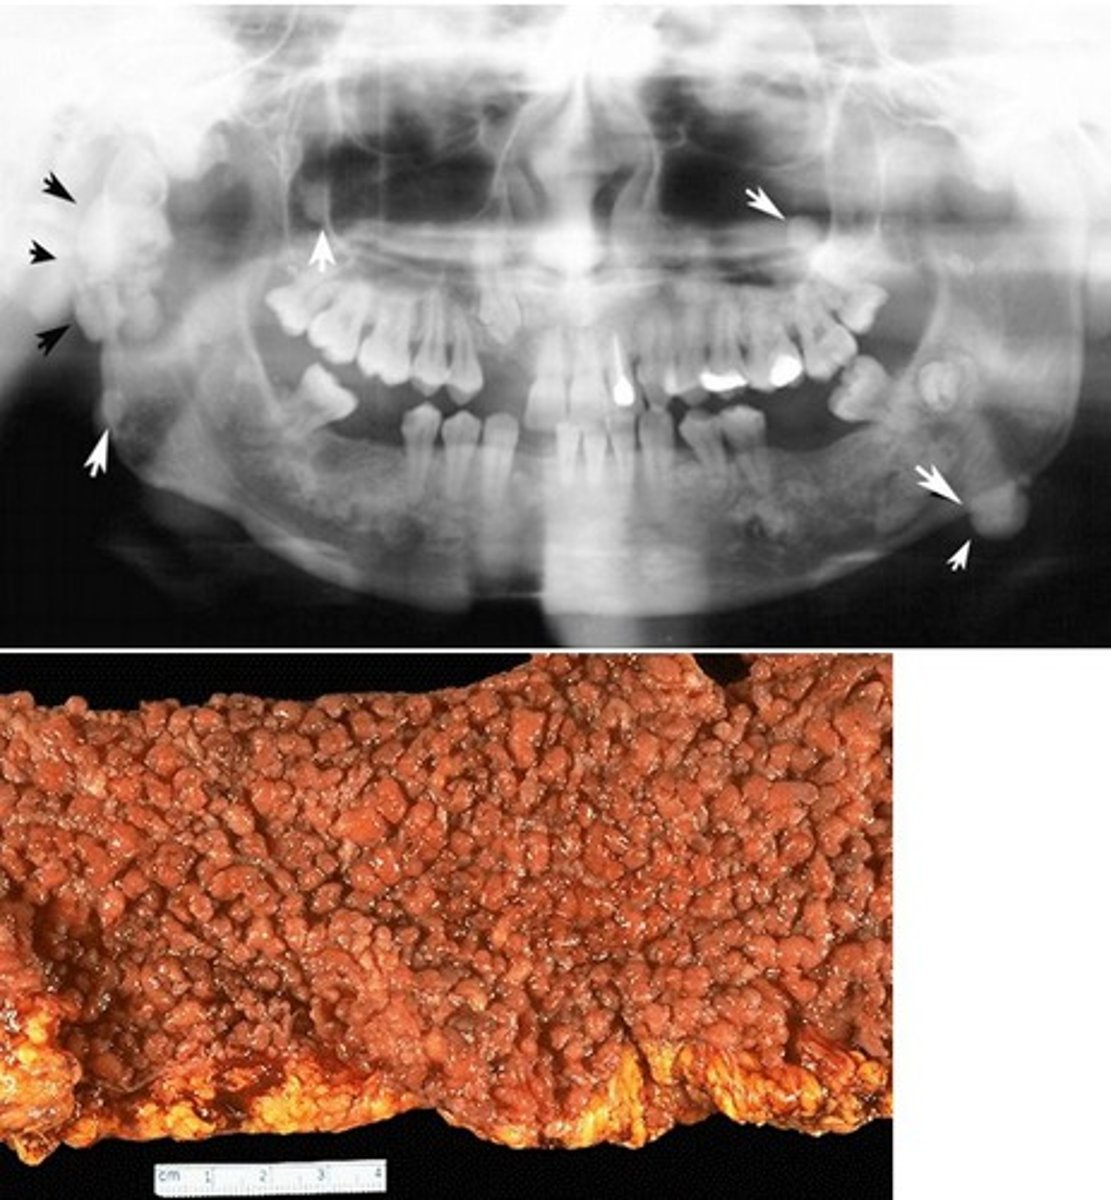

![<p>Wet Beriberi</p><p>(Thiamine [B1] Deficiency)</p>](https://knowt-user-attachments.s3.amazonaws.com/b5392328-09d7-4cf3-805f-45d95919235d.jpg)

Dry eyes, dry mouth, arthritis, recurrent dental caries

Sjogren syndrome

(autoimmune destruction of exocrine glands)

Can have RF, Anti-SSA or SSB

Lymphocytic sialadenitis

Risk of B-cell lymphoma